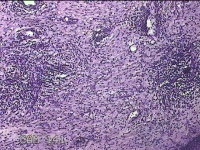

宫颈锥切物

性别

女

年龄

36岁

临床诊断

宫颈CIN2 宫颈乳头病毒感染

一般病史

检查发现CIN21个月。

标本名称

大体所见

灰白粉红色组织5.5x1.3x0.8cm一块,表面糜烂,切面灰白粉红色,质软,另有灰白粉红色组织2.3x2x0.3cm一堆,表面糜烂,切面灰白粉红色,质中。